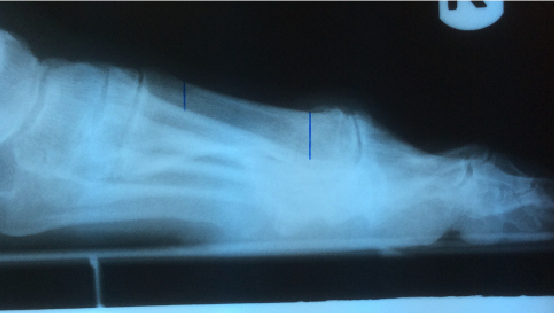

Metatarsu

s primus elevatus is basically a radiographic finding that theoretically depicts the position of the first metatarsal relative to the lesser metatarsals at the midstance phase of the gait cycle.18 In metatarsus primus elevatus, the first metatarsal is elevated to an abnormal position. However, there is no agreement as to the degree that this elevation is truly “abnormal” or pathologic. Some authors have noted that metatarsus primus elevatus can be present in normal, healthy feet with no evidence of hallux rigidus.19

Many authors have connected metatarsus primus elevatus as a causative factor for hallux rigidus. Meyer reviewed radiographs of 120 patients and found that hallux rigidus findings did correlate with the presence of metatarsus primus elevatus.20 Roukis determined the mean first to second metatarsal elevation to be 5.8 mm in a hallux rigidus group, which was higher than in patients with other foot pathologies.21 Bouaicha and coworkers attempted to standardize techniques to measure alignment of the first metatarsal on lateral radiographs and found that elevation of the first metatarsal greater than 5 mm was predictive of hallux rigidus.17

The fact that hallux rigidus and metatarsus primus elevatus seem to go together when looking at lateral radiographs reaffirmed the long held notion that hypermobility and elevation of the first ray must be a primary cause of hallux rigidus. However, two studies have raised the question about whether such a cause-effect relationship really exists. Horton and coworkers studied radiographs of patients with and without hallux rigidus, and found no difference in alignment of the first ray between the two groups.18 In cases of severe hallux rigidus, the metatarsus primus elevatus increased significantly, suggesting to the authors that elevation of the first metatarsal occurs as a result of hallux rigidus and not vice versa.

Bouaicha and coworkers further studied the role of metatarsus primus elevatus and hallux rigidus.17 They observed that some of the conflicting results of previous studies of metatarsus primus elevatus were due to unreliable measurement techniques of radiographs taken of patients with hallux rigidus. Bouaicha and colleagues described a new measurement technique to measure elevation of the first metatarsal relative to the second metatarsal. With this technique, a correlation between metatarsus primus elevatus and hallux rigidus was present, but the authors could not determine the cause-effect relationship.

However, a more interesting finding was reported in the Bouaicha study regarding the position of the hallux relative to the first metatarsal.17 This angular relationship in the sagittal plane, described as the first metatarsal dorsiflexion angle, showed a significant reduction (i.e. plantarflexion) in patients with hallux rigidus. Furthermore, there was a significant correlation with plantarflexion of the hallux and elevation of the first metatarsal in patients with hallux rigidus. The authors speculated that tensioning of the flexor hallucis longus tendon could be responsible for retrograde metatarsus primus elevatus.